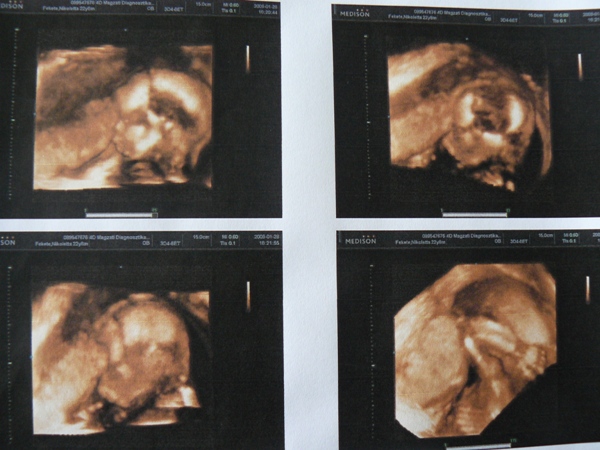

jobb alsó kép

jobb alsó kép

12+2 hetesen pociban_1

12+2 hetesen pociban_1

12+ 2 hetesen pociban_2

12+ 2 hetesen pociban_2